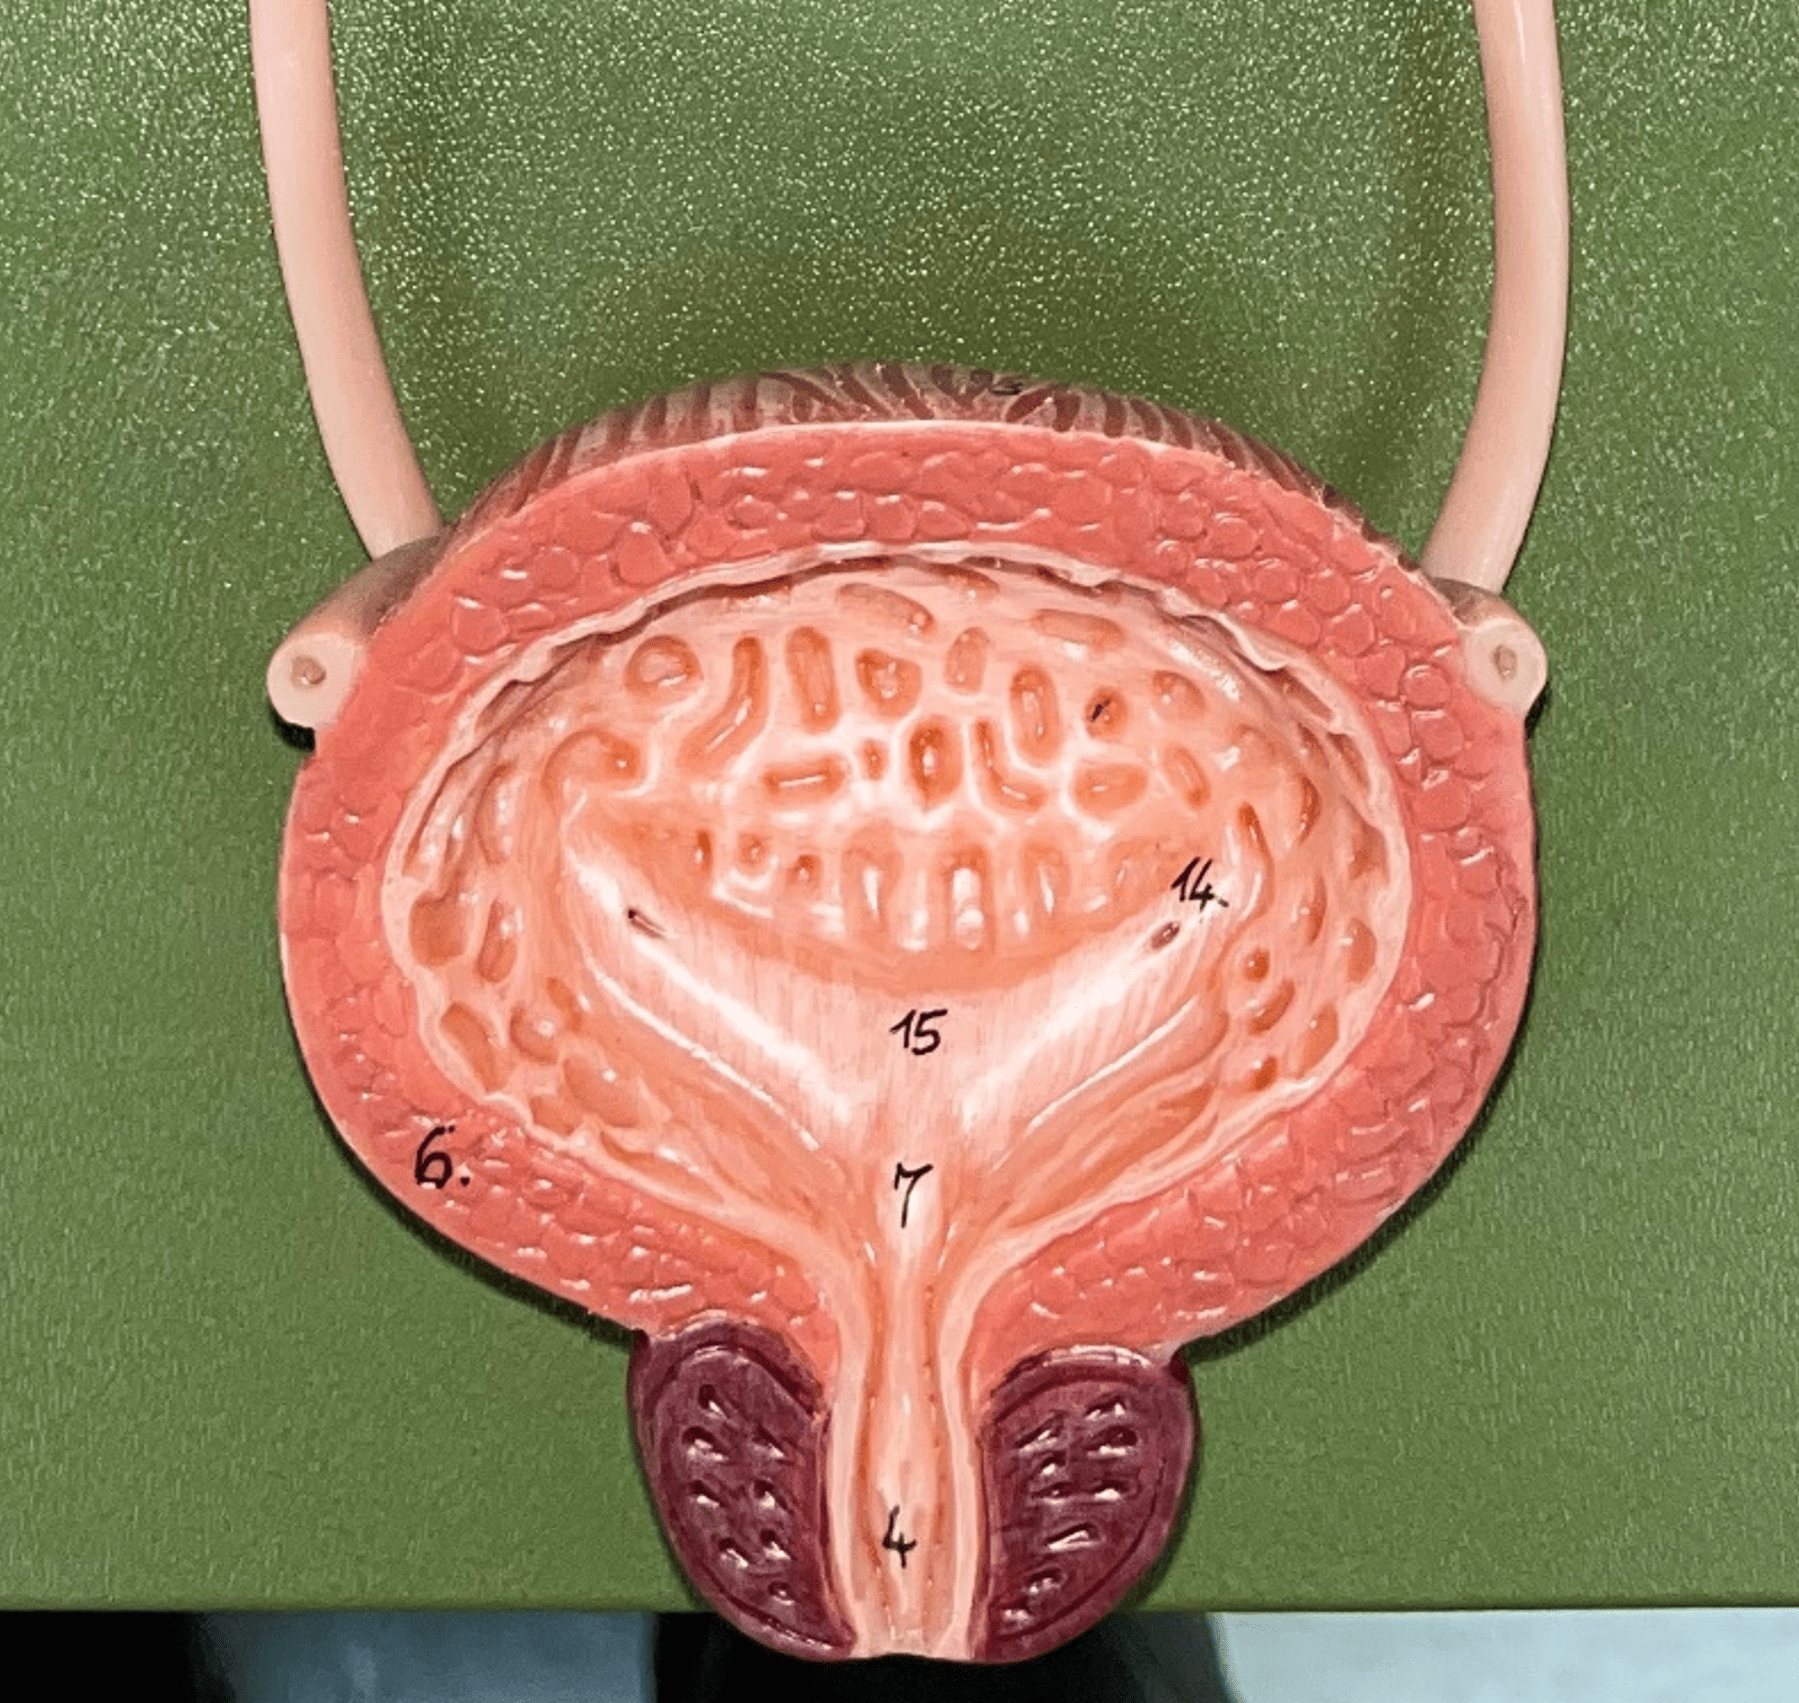

urinary bladder

The hollow sac organ that collects and temporarily stores urine.

rugae

• Part of the urinary bladder.

• Folds of the mucous membrane of the bladder.

• Flattens as the bladder fills with urine to increase capacity.

• Folds of the mucous membrane of the bladder.

• Flattens as the bladder fills with urine to increase capacity.

trigone

• Part of the urinary bladder.

• The triangle formed by the ureteral openings and internal urethra orifice.

• The triangle formed by the ureteral openings and internal urethra orifice.

ureteral opening

• Part of the urinary bladder.

• A posterior opening on either side of the of the bladder led in by the ureters.

• A posterior opening on either side of the of the bladder led in by the ureters.

internal urethral orifice

• Part of the urinary bladder.

• The anterior opening of the bladder leading to the urethra.

• The anterior opening of the bladder leading to the urethra.

detrusor muscle

• Part of the urinary bladder.

• The muscularis of the bladder.

• Contracts to expel urine from the bladder.

• The muscularis of the bladder.

• Contracts to expel urine from the bladder.

urethra

A tubular organ carrying urine from the bladder to the exterior during micturition (voiding of urine).

internal urethral sphincter

\

• Part of the urethra.

• A circular layer of circular smooth muscle located just after the internal urethral orifice.

• Involuntary muscle allowing urine to flow outward.

• Part of the urethra.

• A circular layer of circular smooth muscle located just after the internal urethral orifice.

• Involuntary muscle allowing urine to flow outward.

external urethral sphincter

• Part of the urethra.

• A layer of skeletal muscle located just before the external urethral orifice.

• Voluntary muscle allowing urine to flow out to the exterior.

• A layer of skeletal muscle located just before the external urethral orifice.

• Voluntary muscle allowing urine to flow out to the exterior.